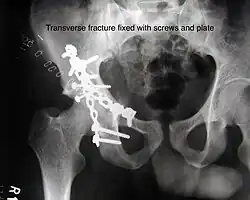

Transverse fracture fixed with screws and plate